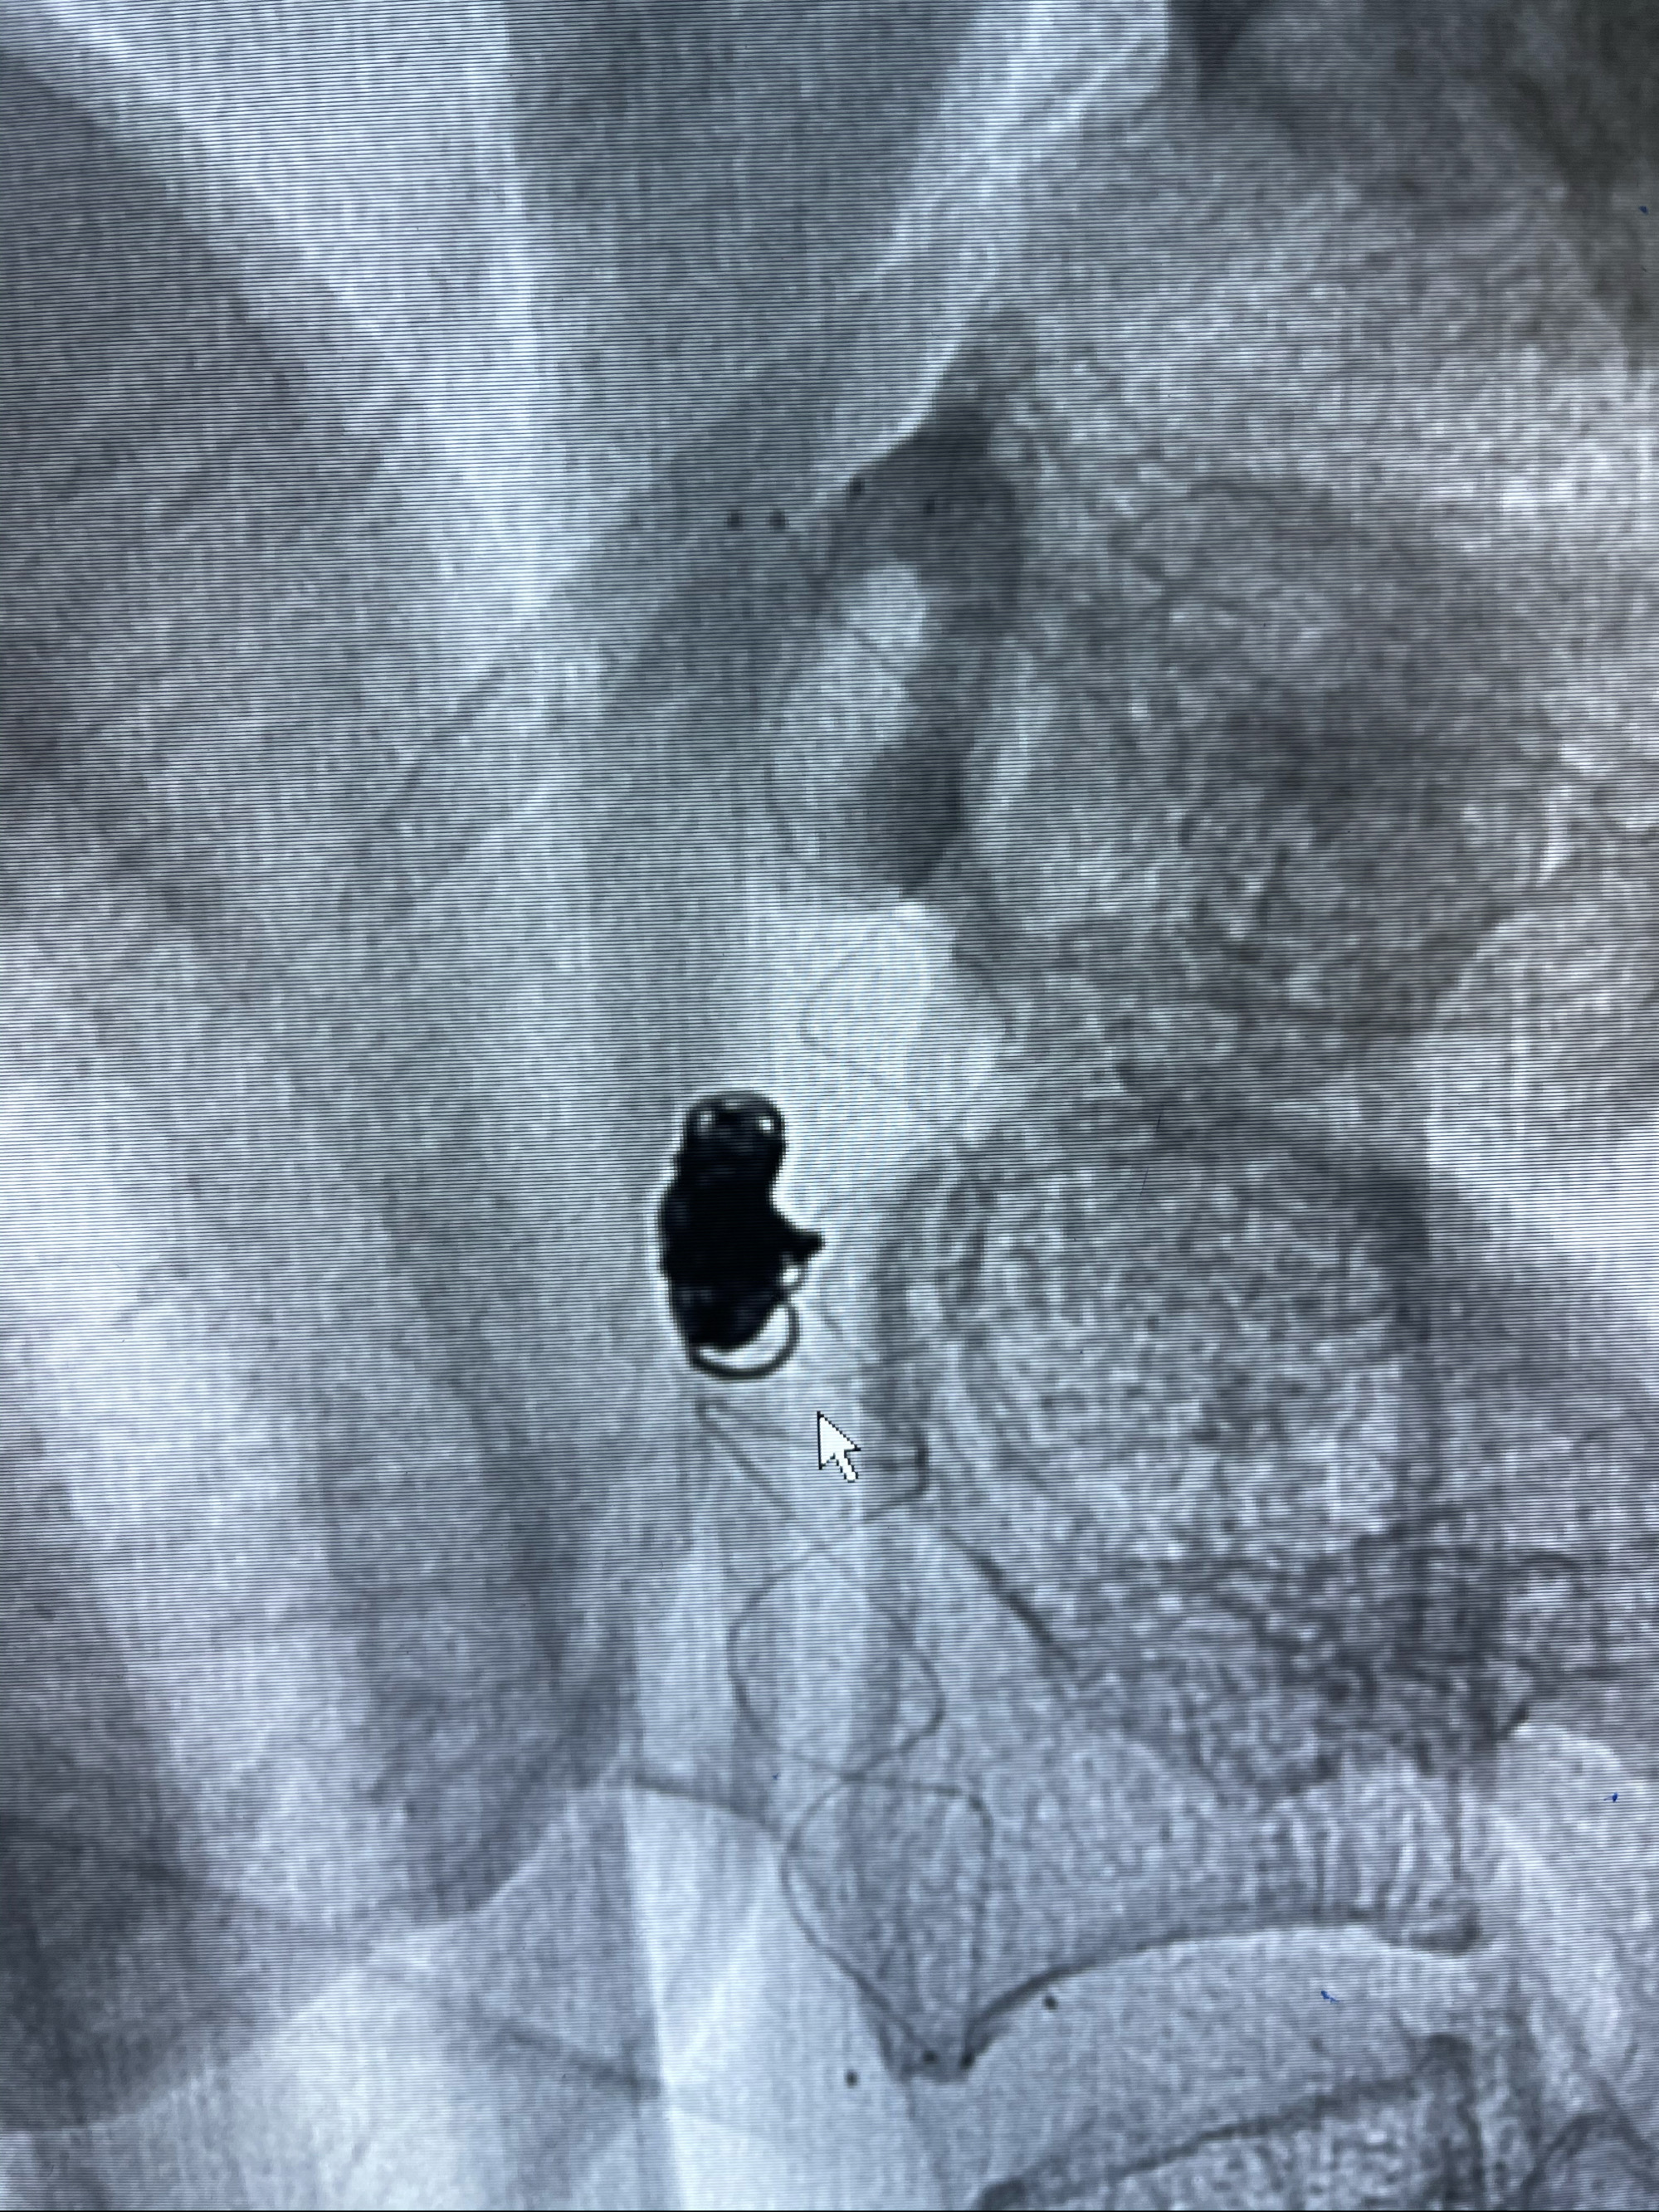

2021-03-08行全脑血管造影

工作角度造影

即刻造影